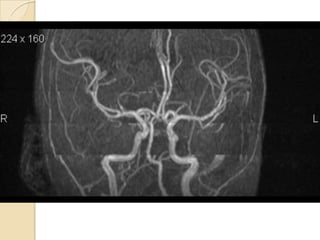

Arteries of the brain (cranial view) - MRA

1. Anterior cerebral artery

2. Anterior communicating artery

3. Basilar artery

4. branches (in insula) of middle

cerebral artery

5. Cavernous portion of internal

carotid artery

6. Cervical portion of internal carotid

artery

7. Genu of middle cerebral artery

8. Intracranial (supraclinoid) internal

9. Middle cerebral artery

10. Ophthalmic artery

11. Petrous portion of internal carotid

12. Posterior cerebral artery

13. Posterior cerebral artery in ambient

cistern

14. posterior cerebral artery in

interpeduncular cistern

15. Posterior communicating artery

16. Posterior inf cerebellar artery.

17. Quadrigeminal portion of posterior

18. Superior cerebellar artery

19. Vertebral artery